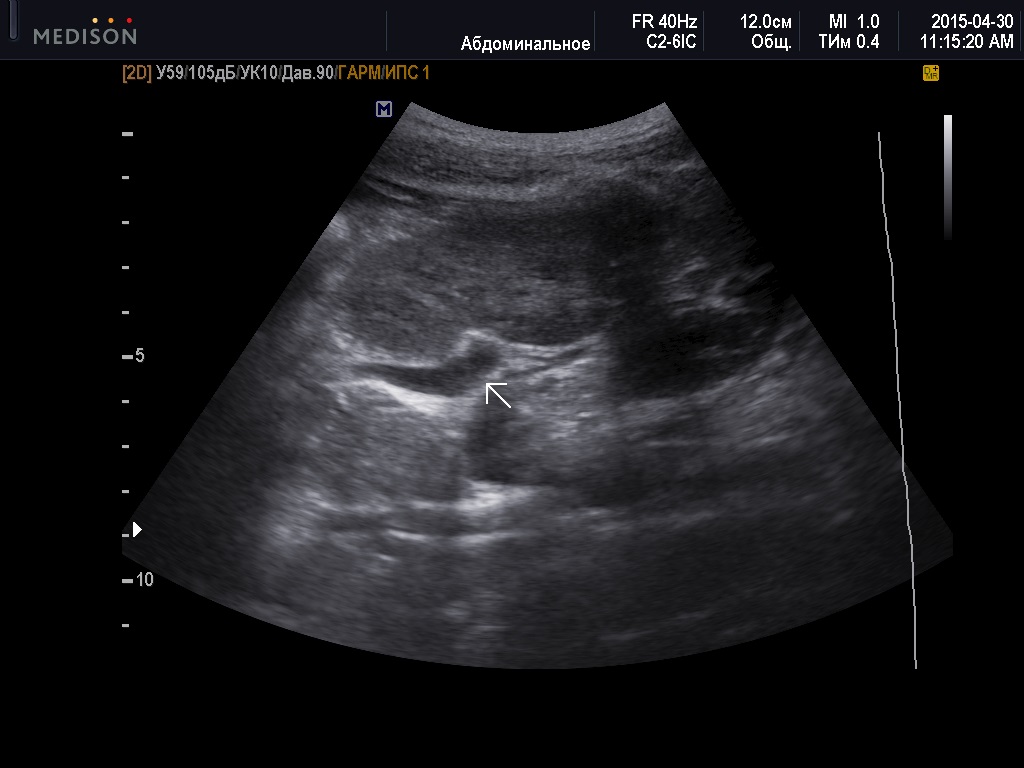

Случай 2015 года, девочка на амбулаторно приёме, бросилось в глаза "пульсирующее" уретероцеле слева. При детальном осмотре уретеро-везикального соустья в режиме ЦДК обнаружен выброс из 3-х мочеточников.

При этом в левой почке определялась одна лоханка, расположенная несколько ниже обычного положения, вторая не визуализировалась. Ее стало возможно видеть в активную фазу заполнения и при пробе с диуретиком.

Левая почка при первичном обследовании